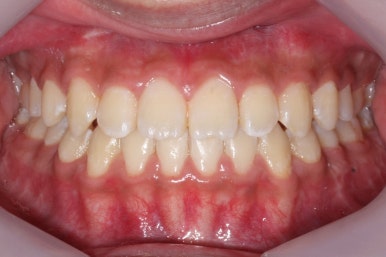

위 사진들은 부산주걱턱교정 키다리아저씨치과에 내원하셨을 당시의 입안 모습입니다.

입 안의 모습에서도 주걱턱의 특징으로는

하악이 앞으로 나와있습니다.

윗니는 뻐드러지고 아래 앞니는 뒤쪽으로 쓰러져 있습니다.

교합이 맞지 않습니다.